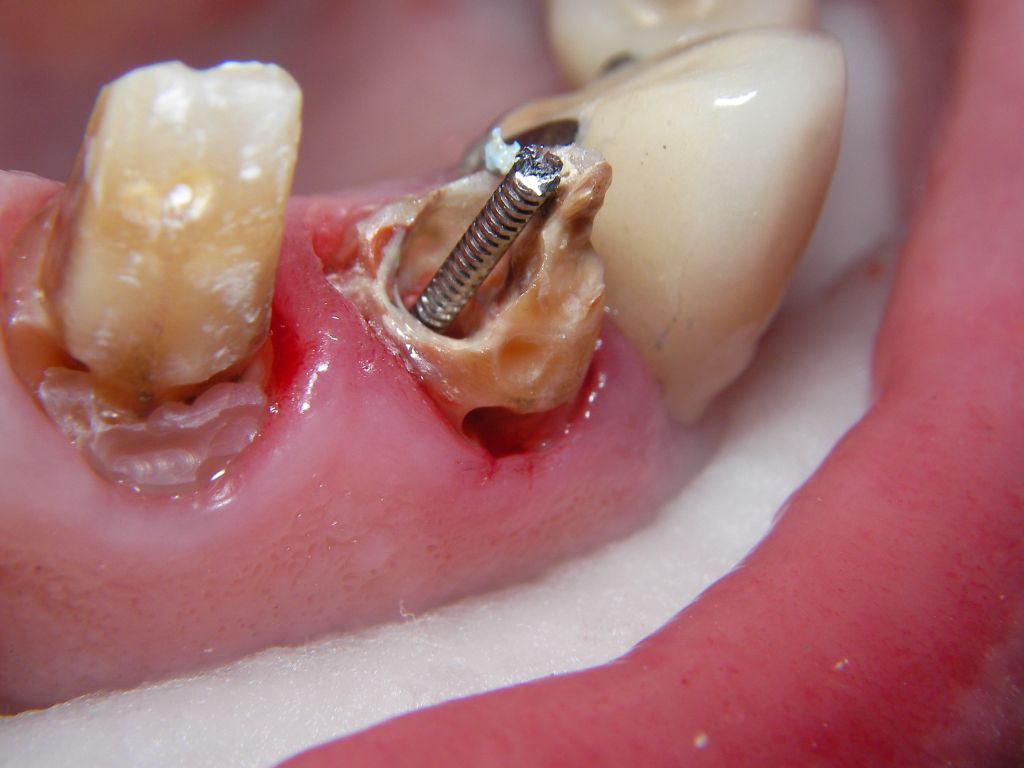

Weil auch die anderen Schneidezahnkronen (12-22) durch Randreparaturen und den schlechten Randschluß erneuerungsbedürftig aussahen, wurden 4 Einzelkronen geplant. Vorher hieß es aber noch, die schlechte Wurzelfüllung im Zahn 12 (Röntgenbild links) besser zu machen. Hierfür wurden am 17.2.06 die alten Kronen 11 und 12 entfernt. Rechts das Bild nach Entfernung von alten Füllungen und Karies. | |

Links nach Wurzelfüllung beim Einpassen des Titanstiftes. Rechts dann der schon provisorisch beschliffene Amalgamaufbau im Zahn 12. |

Der Abschluß der Sitzung am 17.2.06 waren 2 provisorische Kronen auf Zahn 11, 12. Das provisorische Material war hier wegen der besseren Farbanpassung Herculite XRV. Rechts sieht man auch die alten Kronen 21 und 22 und die von mir früher reparierten Randdefekte. |

Am 28.2.06 erfolgte die endgültige Präparation (das "Beschleifen") aller 4 Zähne. Links das Modell, auf dem die Kronen gefertigt worden waren. Rechts kurz vorm Zementieren der Kronen am 13.3.06. Aus der Längendifferenz der Zähne rechts und links kann man darauf schließen, daß die Präparation tief unter dem Zahnfleisch erfolgen mußte. |